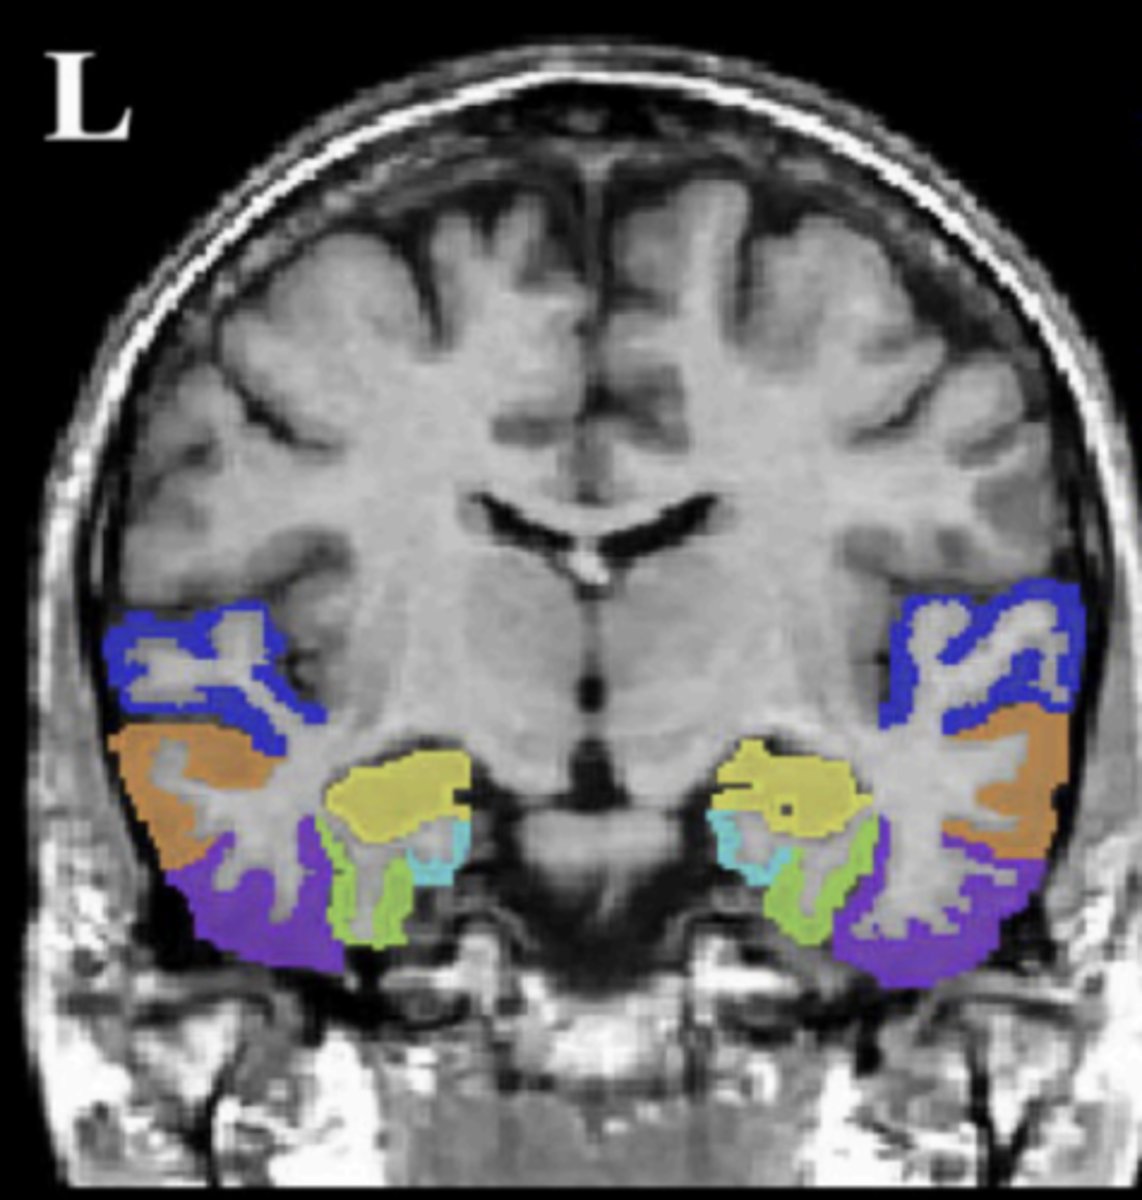

temporal lobe (coronal view)

insula

circled in red, next to STG

superior temporal gyrus (STG)

dark blue area

middle temporal gyrus (MTG)

orange area

inferior temporal gyrus (ITG)

purple area

fusiform gyrus (FG)

green area

parahippocampal gyrus (PHG)

light blue area

hippocampus (HIPP)

yellow area